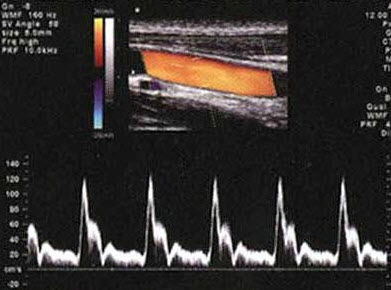

82、判断题

如图,颈动脉壁上异常光团提示动脉壁粥样斑块硬斑形成。